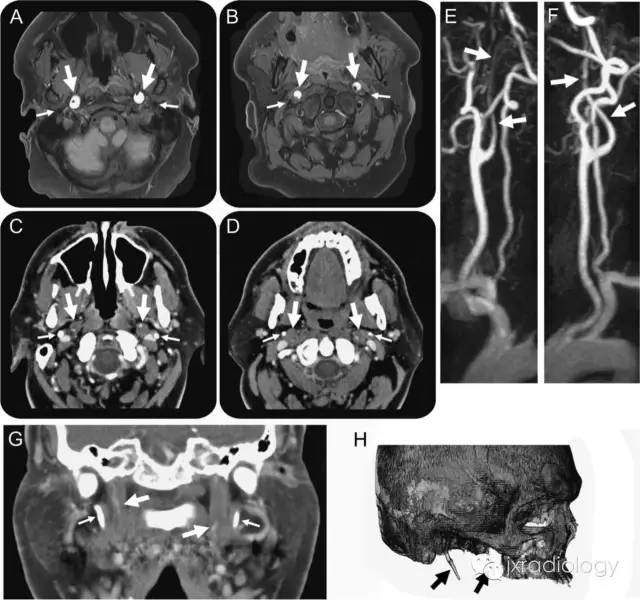

Bilateral cervical internal carotid artery dissections in Eagle syndrome:

双侧颈内动脉夹层